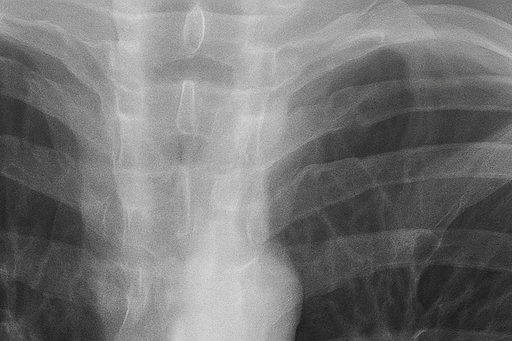

(2) 흉부 X선 검사

흉부 X선 촬영은 가장 기본적이고 신속한 진단 방법입니다. X선 영상에서 공기가 찬 부위는 검게 보이며, 허탈된 폐는 중심 쪽으로 쪼그라든 형태로 나타납니다. 이를 통해 폐 허탈의 범위와 기흉의 크기를 확인할 수 있습니다. 그러나 폐 상부의 작은 공기집(bleb)은 X선으로 잘 보이지 않아, 필요한 경우 흉부 CT 검사를 시행합니다.